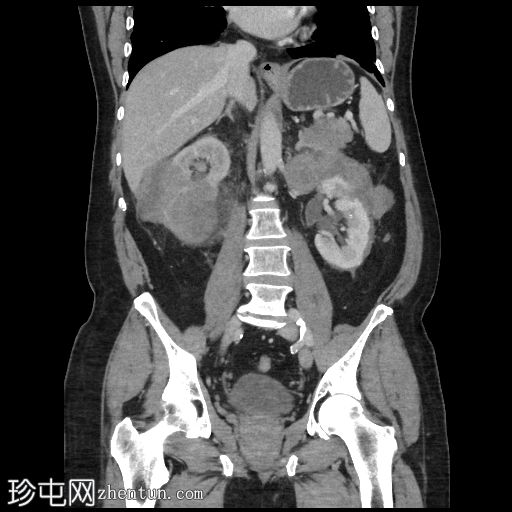

冠状位增强扫描(门静脉期)

右肾可见不规则分叶状低密度浸润性病变,超出肾包膜,并与右肝下叶相邻。

左肾可见弥漫性浸润性病变,以上极为中心。左肾浸润性病变与胰尾相邻,胰尾可能受累,表现为胰腺后缘不规则、脂肪间隙消失。此外,浸润性病变与左侧肾上腺外侧肢相邻。

脾脏下极可见一密度不明、呈分叶状/浸润性改变的肿块。